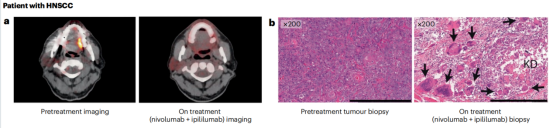

免疫检查点抑制剂:针对免疫细胞调节检查点的单特异性抗体在癌症患者中显示出了显著的临床疗效。FDA和EMA批准的11种免疫检查点抑制抗体目前正在用于治疗20多种不同类型的癌症,包括肺癌、黑色素瘤、肾细胞癌、头颈部鳞状细胞癌,预计还有几种这些抑制性抗体将在不久的将来获得批准。

免疫检查点阻断抗体通过一般的免疫激活介导癌细胞的杀伤,这种激活有时会被错误地指向健康组织。免疫检查点抑制抗体具有非常明显的不良反应谱,称为免疫相关不良事件(irAEs)。偶尔可能出现严重和潜在致命的毒性。在许多情况下,需要使用糖皮质激素、肿瘤坏死因子(TNF)拮抗剂、霉酚酸酯或其他免疫调节剂进行暂时免疫抑制来控制irAEs。